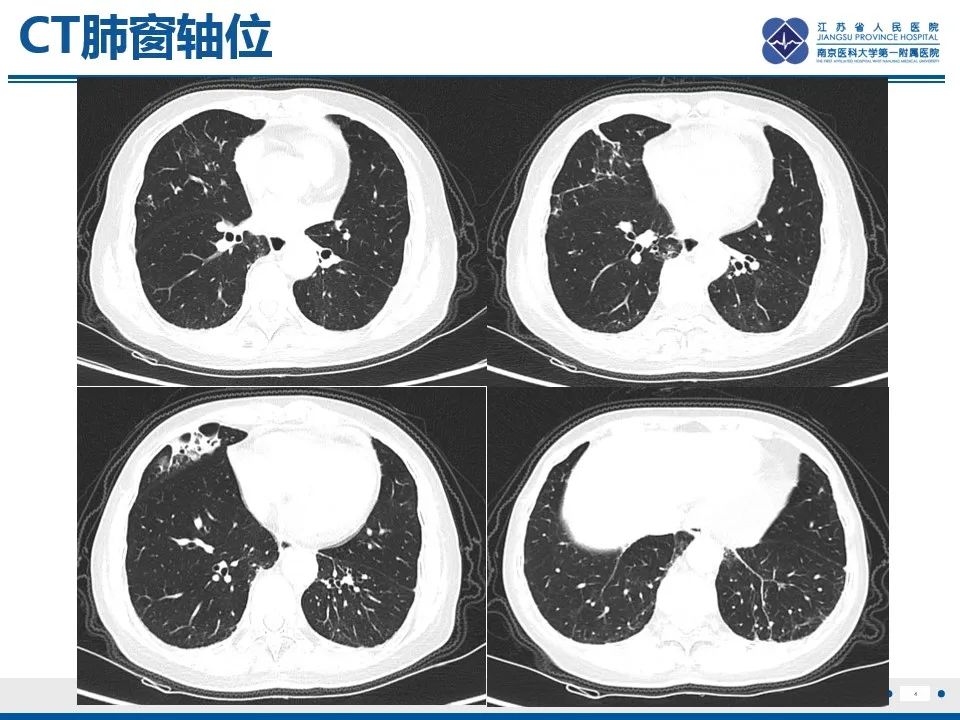

作者:武晨江、陈爱萍

本文首发自江苏省人民医院放射科